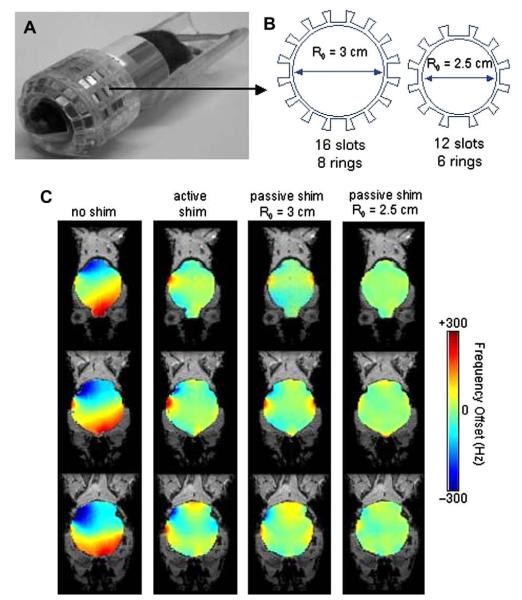

Fig. 8 shows the effects of increasing orders of shim inclusion in the whole-brain least-squares optimization of B0 field homogeneity in the human brain at 3T. It is clear from the field-maps that low-order RT shimming leaves significant residual inhomogeneity. While there is a clear advantage of going from first (B) to second (C) order shimming, with the use of third-order shimming (D), there is significantly less improvement in homogeneity compared to second-order shimming (C).

Fig. 8.

(A) Axial MRI at B0 = 3T of two axial slices encompassing the sinus cavity region, residual inhomogeneity after (B) first order shimming, (C) with the inclusion of second-order shims, (D) with the inclusion of third-order shims.

Fig. 9 similarly shows residual field maps after global shimming of the mouse brain at 9.4T. The residual inhomogeneity here is even more severe than in the human case due to (a) the higher magnetic field strengths of small-animal MR systems and (b) the more complicated air-cavity distributions in the mouse head. Viable high-field, whole-brain, single-shot EPI images of the mouse brain have yet to be demonstrated because of this residual inhomogeneity. This severely limits the quality and temporal resolution of BOLD and DTI studies on the mouse brain.

Fig. 9.

Coronal field inhomogeneity maps of the mouse brain at 9.4T with (A) no shimming, (B) first-order shimming, (C) first and second-order shimming, and (D) first through third-order shimming.